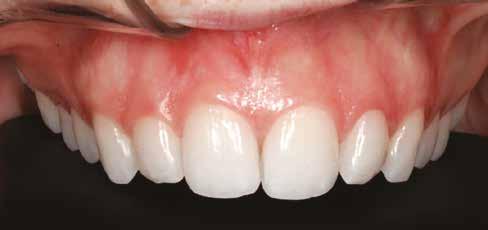

A tényleges protetikai ellátás megkezdése előtt a páciens mosolygás közben látható fogait otthoni fogfehérítés keretei között a kérésének megfelelő A1-es fogszín eléréséig fehérítettük. A fehérítés során a későbbiekben héjakkal ellátásra kerülő fogak színén nem változtattunk. A fogak előkészítése részeként csupán a két felső nagymetsző (1.1,2.1) incizális élét kellett kismértékben redukálni. A többi felső front fog (1.3,1.2,2.2,2.3) nem került preparálásra.

A héjak átadását követően kialakuló állapot valósághű módon történő bemutatása érdekében próbapasztát alkalmaztunk (Try-In-Paste; Variolink® Esthetik Try-In-Paste, Ivoclar Vivadent) (11. ábra). A próba során ellenőrizzük a héjak színét, formáját és transzparenciáját. A próbapaszta alkalmazásának egyik lényeges pontja, hogy a paszta színe egyezzen meg a végleges beragasztás során alkalmazni kíván ragasztóanyag színével. A héjak végleges rögzítése során mindig adhezív rendszereket használunk.

nak megfelelően – előkészítjük (orthofoszforsavval történő savazás, lemosás, szárítás és bond réteggel történő fedés). Ezzel egyidejűleg a ragasztásra kerülő héjak is előkészítésre kerülnek (hidrofolysavval történő savazás, lemosás, szárítás, szilanizálás, bond réteggel történő fedés, és végül az alkalmazni kívánt ragasztóanyag felvitele). Ezután a héjakat a fogak felszínén egyesével pozicionáljuk, majd néhány másodpercen keresztül polimerizációs lámpa segítségével megvilágítjuk. Ezt követően a kifolyó ragasztófelesleget eltávolítjuk, majd elvégezzük a restaurátumok végső polimerizálását. A héjak végleges rögzítését követően az esetlegesen visszamaradt ragasztómaradványok eltávolításra kerülnek, valamint ellenőrizzük az okklúzió és artikuláció közben létrejövő fogérintkezéseket. Az optimális esztétikai eredmény biztosítása érdekében kiemelt jelentősége van a papillák helyreállításának (rózsaszín esztétika). A modern fogorvoslás egyik kiemelt célja a fehér- és rózsaszín esztétika közti harmonikus egyensúly megteremtése. A papillák színe, nagysága és szimmetrikus megjelenése meghatározó szerepet tölt be a rózsaszín esztétika kialakításában. Az íny lefutása ugyancsak rendkívül jelentős mértékben befolyásolja a páciens fogazatának esztétikus megjelenését.